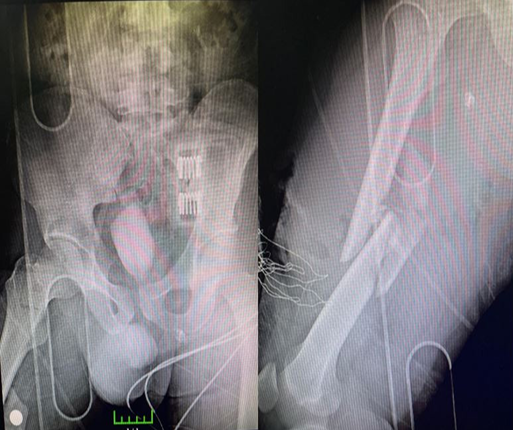

Figure 1. 38-year-old male patient. Applying to the emergency room after a traffic accident. A femoral neck fracture and an ipsilateral femoral shaft comminuted fracture are present

Figure 2. First, the cannula is screwed for the femoral neck fracture of the patient. An external fixator is applied for a femoral shaft fracture with the idea of damage-controlled surgery

Figure 3. First-year anteroposterior X-ray images of the patient who was followed up postoperatively